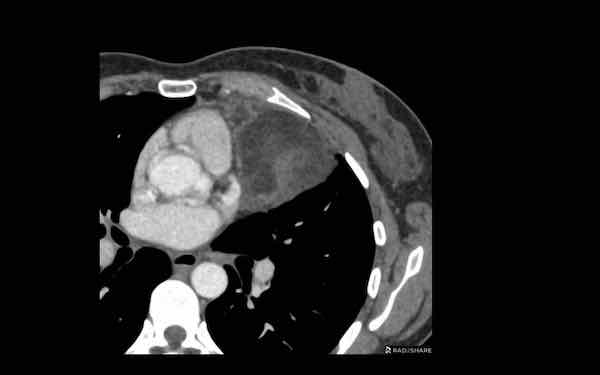

Các hình ảnh này của một nam giới 71 tuổi.

Trên CT ngực, tình cờ phát hiện một khối ở tuyến ức.

Hãy phân tích các hình ảnh. Nhận định của bạn là gì?

Hình ảnh

Một phần tổn thương có ngấm thuốc cản quang và có một số vôi hóa, có thể nằm ở thành nang.

Khi một tổn thương tuyến ức có thành phần đặc, nguyên tắc là… “khi còn nghi ngờ, hãy phẫu thuật cắt bỏ”.

Tổn thương đã được phẫu thuật cắt bỏ dựa trên kết quả CT và kết quả giải phẫu bệnh cho thấy đây là u tuyến ức dạng nang.